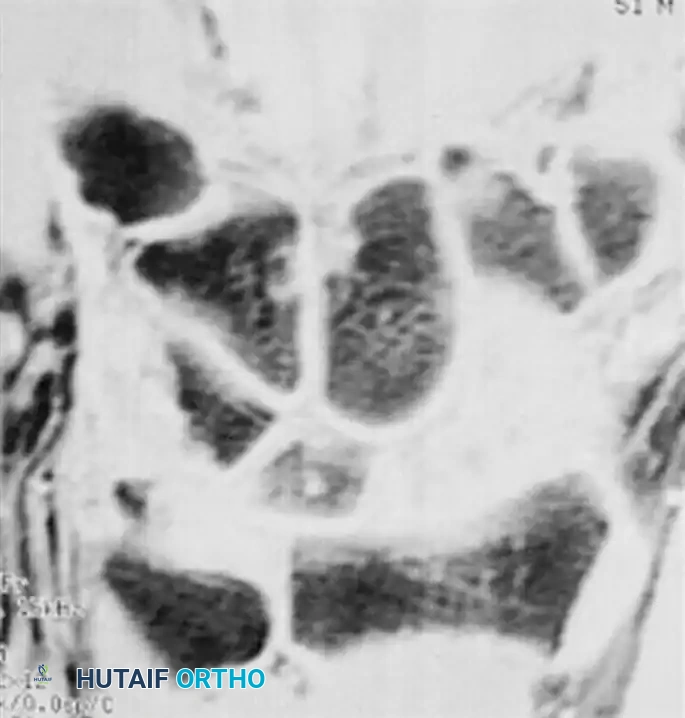

Magnetic Resonance Imaging (MRI) and Computed Tomography (CT)

MRI is currently the gold standard for detecting occult scaphoid fractures. Gaebler et al. reported 100% sensitivity and specificity using MRI to diagnose occult scaphoid fractures at an average of merely 2.8 days post-injury.

Furthermore, MRI—especially with gadolinium enhancement—is invaluable in assessing the vascular status of the proximal pole in established fractures or nonunions.

(A) MRI demonstrating an acute, occult scaphoid waist fracture not visible on plain radiographs. (B) Gadolinium-enhanced MRI evaluating the vascularity of the proximal pole, critical for surgical planning.

While MRI is superior for detecting edema and vascularity, Computed Tomography (CT) scans reconstructed in the sagittal and coronal planes of the scaphoid are the imaging modality of choice for assessing fracture displacement, angulation (humpback deformity), and progression of union.